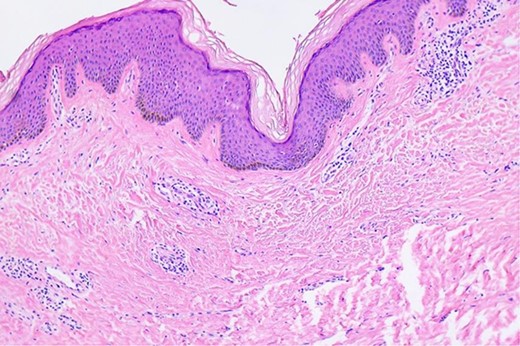

After refining the related clinical exams, this skin mass was resected under general anesthesia. The final histopathological examination showed cystic wall lined with stratified squamous epithelium, a granular layer containing keratin and subcutaneous fibrous tissue hyperplasia without any nuclear atypia (Fig. 3). The patient provided informed consent for the publication of his clinical data and accompanying images. Postoperatively, the patient showed good recovery.

Microscopic findings of the epidermal inclusion cyst. A cystic lesion is lined by benign stratified squamous epithelium filled with abundant lamellated basket weave keratin (hematoxylin and eosin staining ×40).